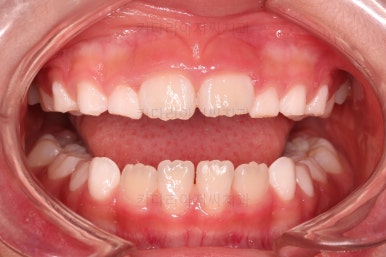

1. 초진

부산어린이교정 키다리아저씨치과에 처음 내원했을 당시의 입안의 모습입니다.

앞니가 거꾸로 물리는 전형적인 앵글씨 3급 부정교합 환아의 모습이었습니다.

아직 유치가 많이 남아 있었꼬, 아래 앞니는 4개가 영구치 맹출, 윗니는 2개가 영구치 맹출 상태였습니다.